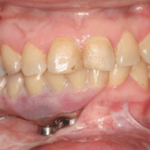

On the day of the surgery two surgical teams simultaneously resect the mandible and harvest the fibular graft using the previously printed stents, attach the reconstruction plate to the harvested fibular graft and then attach it to the remnant mandible; implants are placed there after using the stent. Following the implant placement there is a waiting period of 3-6 months for the graft to get accepted and implants to osseointegrate simultaneously.A prosthesis is then fabricated.

The use of image-guided surgery and surgical guides decreases the risk and minimises the angulation between prosthetic axis and implant axis and also allows precise planning and accuracy of the rehabilitation15,16.